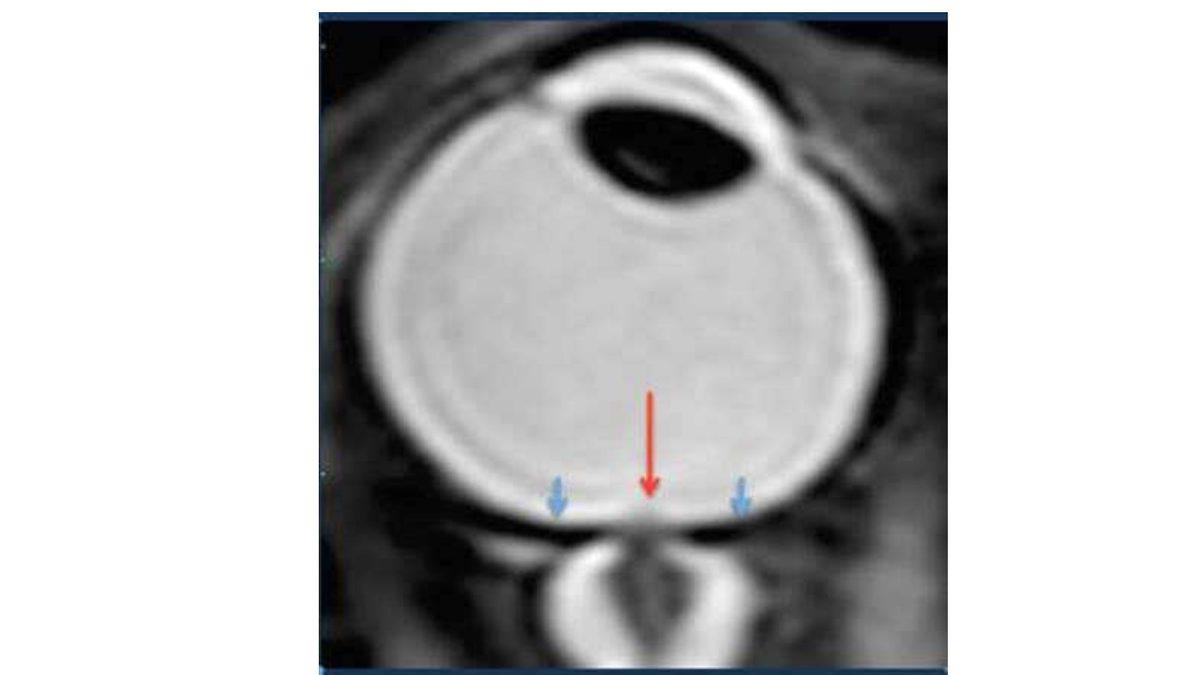

Astronot Michael Bratt’ın gözünü yukarıdaki görselde görebilirsiniz. Uzayda 6 ay kaldıktan sonra bazı şekil değişiklikleri var. Hatta Barratt, kendi sözleriyle şöyle diyor: “Bu, uzaydaki insanların büyük bir yüzdesini etkileyen tıbbî bir problem.”

Bu durum ise gözler dahil kafa bölgesinde basınç artışına ve buna bağlı olarak optik sinire baskı yapıp göz problemlerine, göz küresinin düzleşmesine ve retina üzerinde baskıyla görme kaybına/görme bulanıklığına yol açabiliyor.